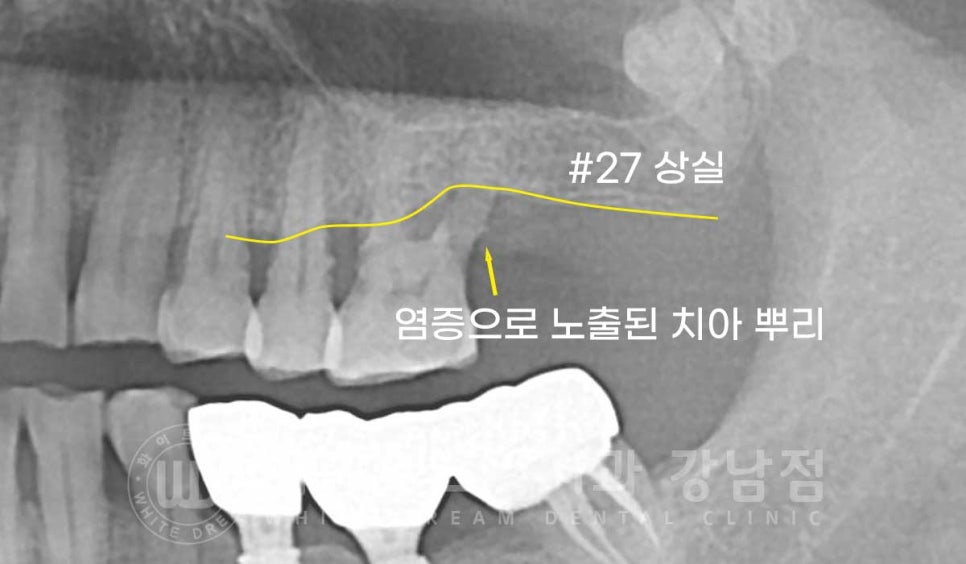

27번 임플란트 옆 26번 치아의 상태도 좋지 못했으나

바로 발치할 정도는 아니고 잇몸치료도 조금 더 사용을 할 수 있을 것으로

판단되어 해당 치아는 잇몸치료를 하면서 동요도를 정기적으로 확인하기로

치료 계획을 세우게 되었습니다.